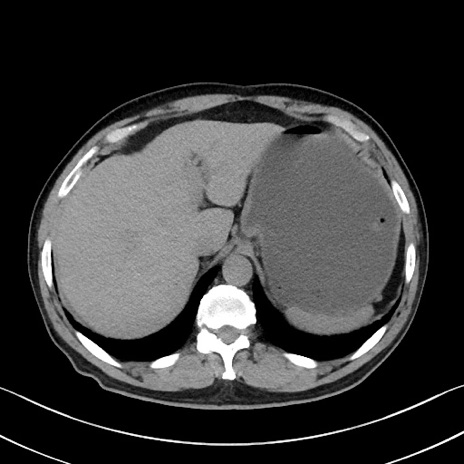

症例35(横断像)

【症例】70歳代 男性

【主訴】腹部膨満、嘔吐

【現病歴】昨日より腹部膨満感出現。本日増悪し、仙痛出現。嘔吐あり、受診。

【既往歴】糖尿病、胆摘後

【身体所見】BP 149/80mmHg、HR 74/min、BT 35.9℃、腹部:膨満、軟、圧痛なし。腸雑音減弱あり。上腹部正中切開瘢痕あり。

【データ】WBC 13500、CRP 1.72